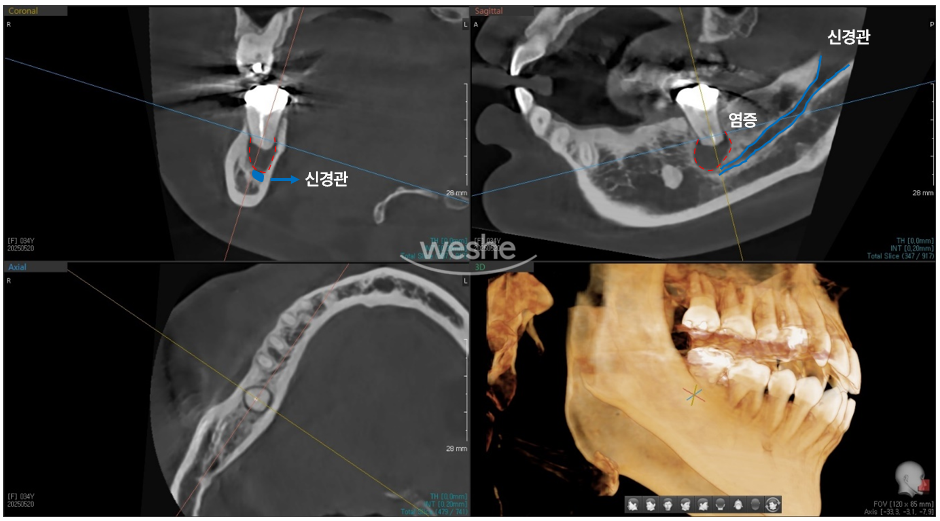

같은 부위의 CT 사진입니다.

아래에 보이는 X-ray에서 빨간색으로 표시된 부위는,

앞서 파노라마 X-ray에서 보였던 검은 음영 부위입니다.

염증으로 인해 치조골(잇몸뼈)이 녹아 생긴 공간입니다.

그리고 파란색으로 표시된 부위는

우리가 흔히 ‘하치조신경’이라고 부르는

inferior alveolar nerve (IAN)입니다.

이 신경은 아래턱의 감각을 담당하는 중요한 구조인데요,

보통은 단단한 뼈 속에 안전하게 보호되어 있습니다.

그런데, 염증이 심해지면

이 신경을 직접 압박하거나,

신경을 감싸고 있는 뼈 자체를 녹여버리는 경우도 생깁니다.

그렇게 되면 마취가 풀리지 않는 듯한 먹먹함이나 감각 이상이 생기기도 합니다.